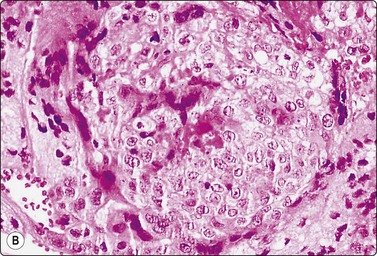

Choriocarcinoma (Fig. 13.39)59,63,66

These tumors most commonly present with symptoms referable to metastases12 and most FNA reports are of extratesticular metastases. Immunostaining for βHCG is helpful to identify syncytiotrophoblastic cells. Large syncytiotrophoblastic cells may also be aspirated from classical seminomas, embryonal carcinomas and mixed TGCT.

image image

Fig. 13.39 Choriocarcinoma

(A) Cluster of cytotrophoblastic and syncytiotrophoblastic cells (MGG, HP); (B) Corresponding tissue section (H&E, IP).